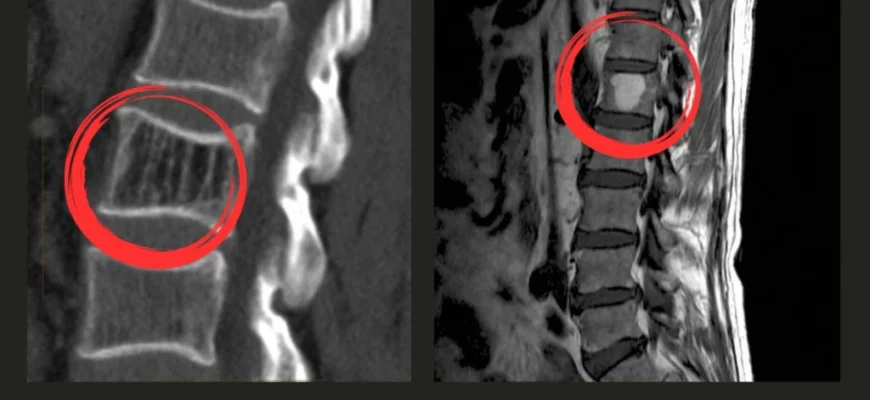

- Магнітно-резонансна томографія (МРТ) — вже серйозніше

- Комп’ютерна томографія (КТ) — не лякайся